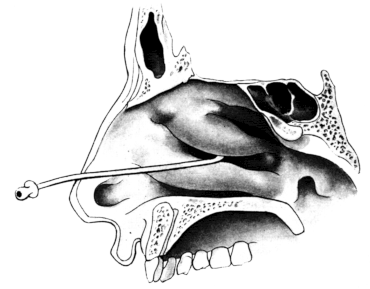

| 333. | Catheterizing the Frontal Sinus | 639 |

| 334. | Radiograph to show the Value of the Röntgen Rays | 639 |

| 335. | Radiograph showing Canula in the Frontal Sinus | 639 |